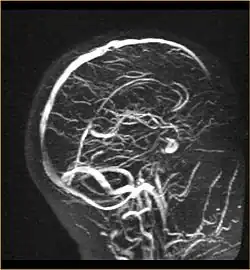

Eine neuere Methode ist die dreidimensionale Rekonstruktion von Magnetresonanztomographie-Aufnahmen nach Kontrastmittelgabe (MR-Angiographie). Diese verdrängt zunehmend die invasive Angiographie. Es existieren daneben qualitativ unterlegene MR-Sequenzen zur Gefäßbildgebung ohne Kontrastmittel (Time-of-flight-Magnetresonanzangiographie). Genauso ist auch mit der Computertomographie nach Kontrastmittelgabe eine Gefäßdarstellung möglich. Umschriebene Änderungen der Mikrozirkulation sind mit Positronen-Emissions-Tomographie, SPECT und mit einem speziellen (sauerstoffsättigungsgewichtetem) MR-Signal (BOLD-Kontrast) darstellbar. Optische Methoden stützen sich auf die Messung der Konzentrationsänderungen von Hämoglobin. Mit ihnen können nur oberflächennahe Blutflussänderungen gemessen werden.

MR-Angiographie der venösen Strombahnen -